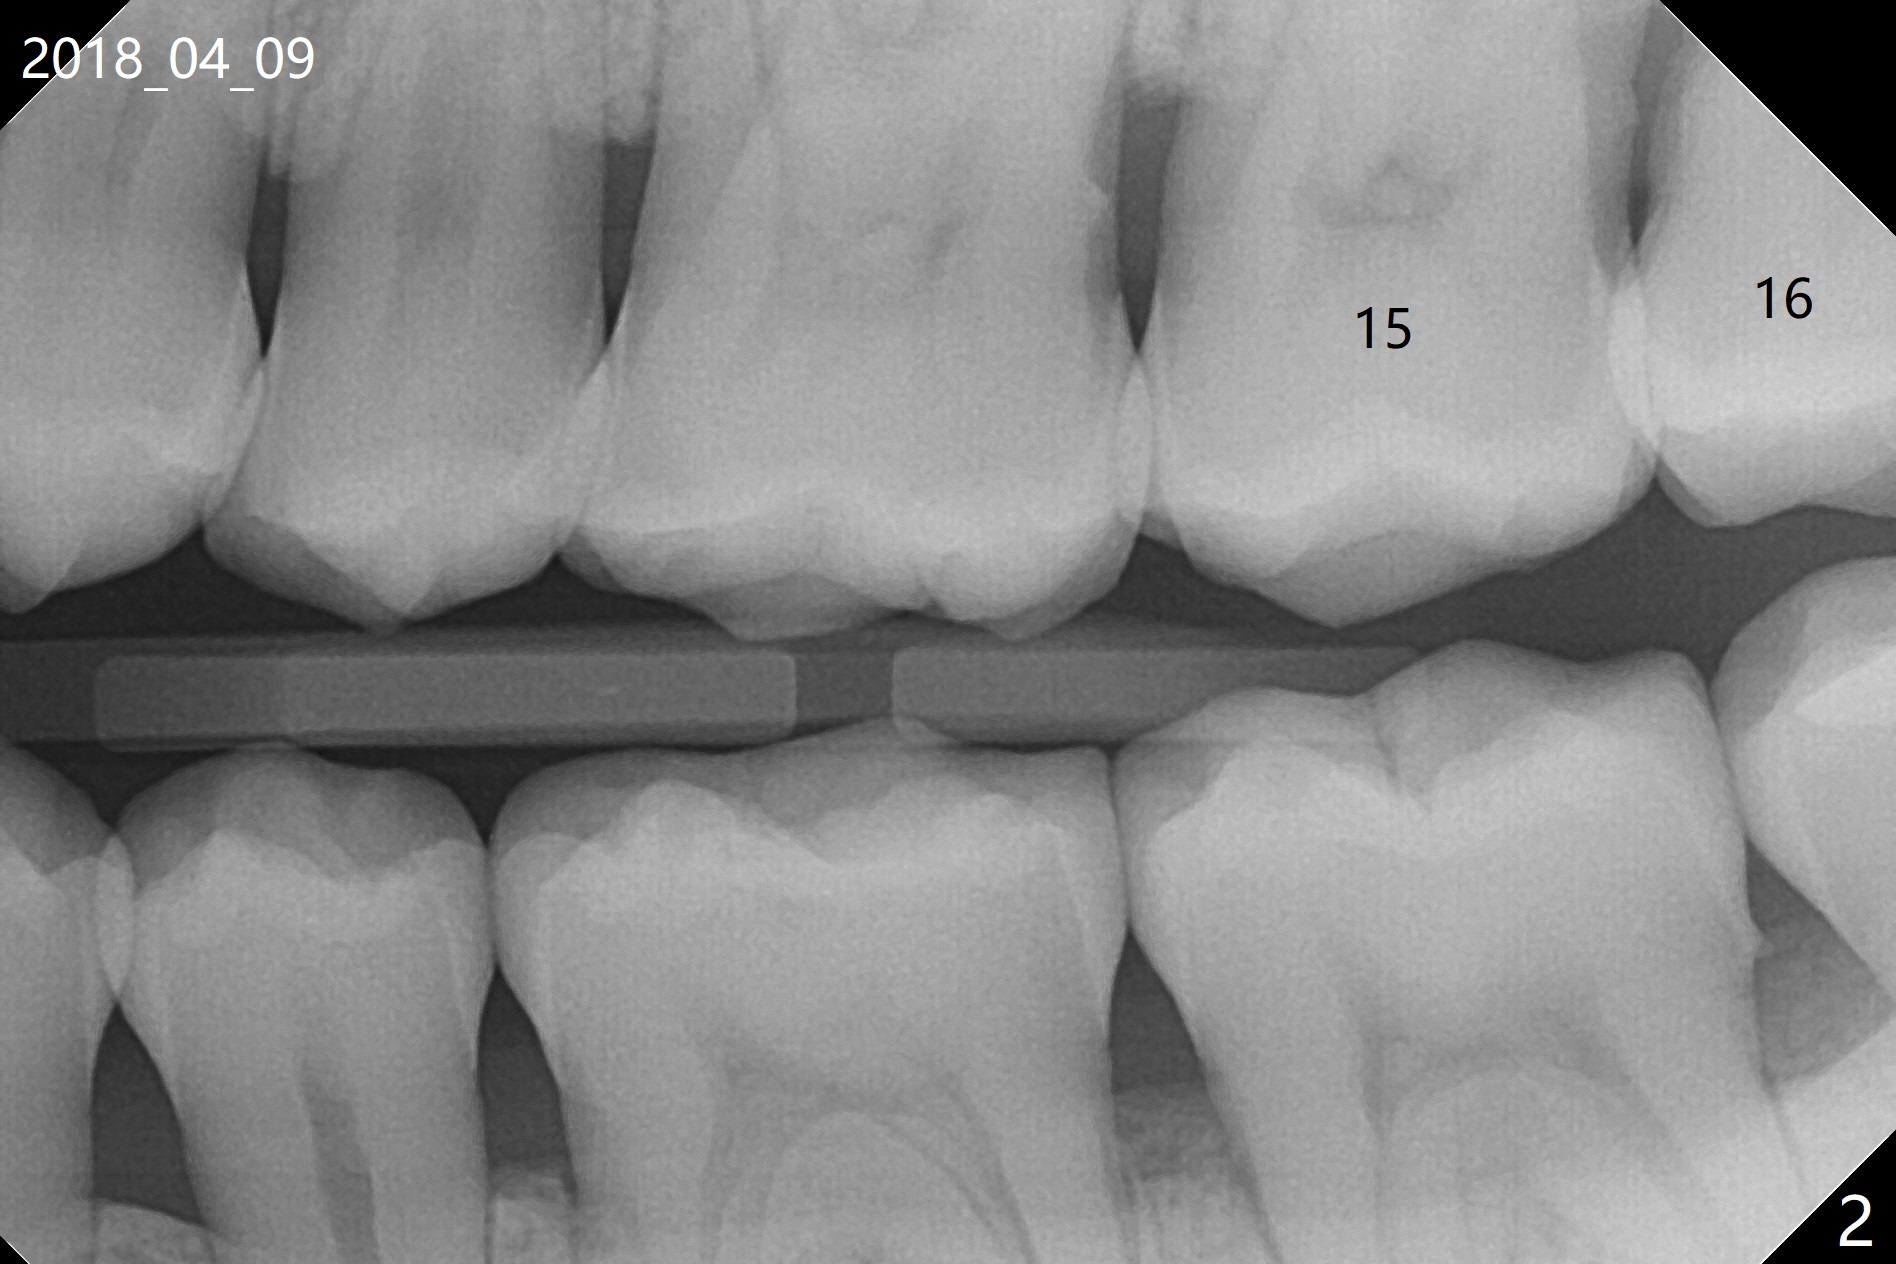

A 35-year-old woman requests extraction of the tooth #1 (food impaction between #1 and 2, Fig.1) and 16 (pain and 6 mm pockets between #15 and 16, Fig.2). In spite of the fact that there is bone loss between #14 and 15 (Fig.3), there is no deep pocket between them. After extraction of #16, SRP is performed in the distal surface of #15 with removal of granulation tissue and application of Endogain. Osteogen plug (Fig.4 O) is placed in the apical and distal portion of the socket of #16 (red dashed line), while allograft (G) against the distal root surface of #15. Finally Collagen plug (C) and 6-month membrane are placed in the opening of the socket, followed by suturing and periodontal dressing. The bone density is high post #1 extraction (Fig.6), related to difficult removal. It appears that bone graft at #16 (^) remains in place 15 months postop. Since no buccal trough is made for extraction, the external oblique ridge is present at #17 and 32 before and after surgery. Bond Apatite is placed with Collagen Plug (Fig.7).